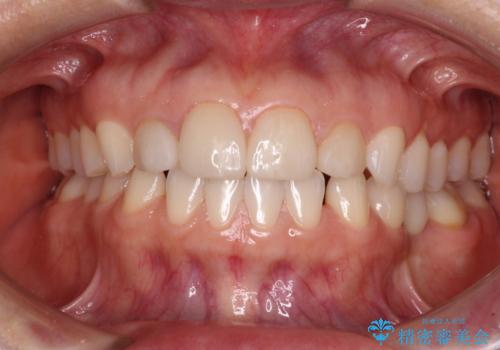

- 大きすぎる上顎前歯と、隙間の空いた下顎歯列を気にして来院された患者様です。

上顎前歯にはセラミッククラウンが装着されており、顔や他の歯と比較して幅の大きい状態でした。

下顎前歯は空隙歯列弓であったので、アンカースクリューとワイヤー装置を用いてスペースを閉じていくこととし、上顎前歯は矯正治療用の仮歯に置き換えた上で、仮歯の大きさを削って小さくしながら、上下前歯部の部分矯正を行うこととしました。

矯正治療後は、仮歯とした上顎前歯をオールセラミッククラウンにて補綴治療を行うこととしました。

日本と海外を拠点に仕事をされていらっしゃるため、数ヶ月治療があいてしまうことがあり、期間はかかりましたが、2年間で望み通りの前歯に仕上げることができました。